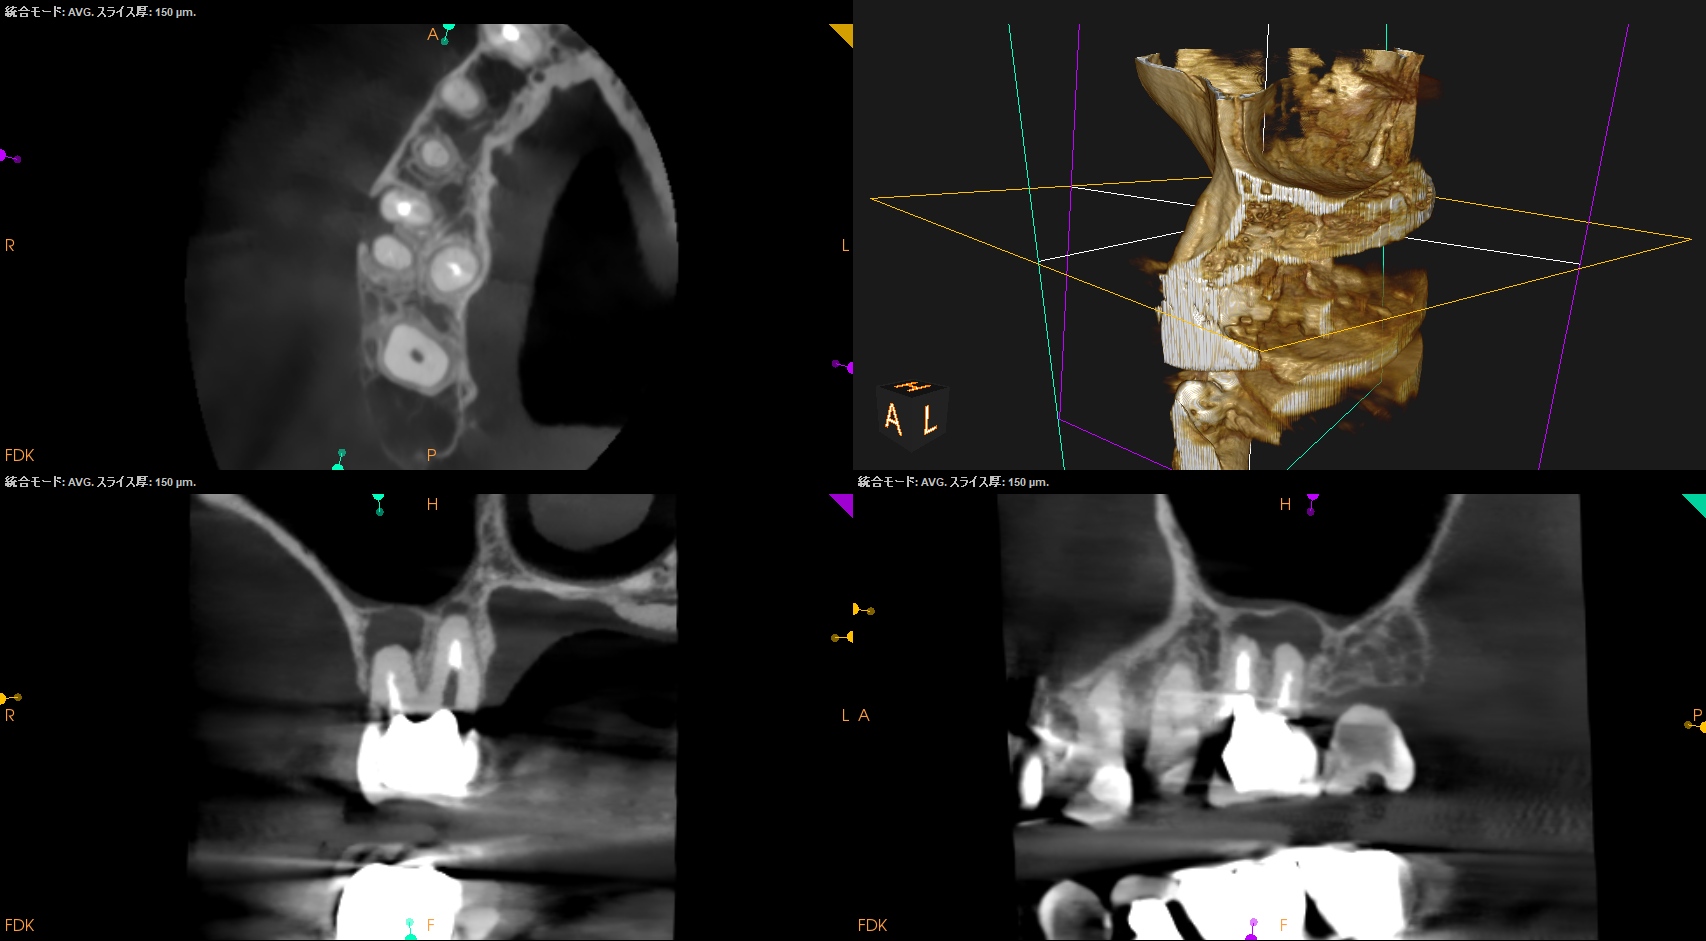

術後にPA, CBCTを撮影した。

#3

MB

DB

P

#14

#16